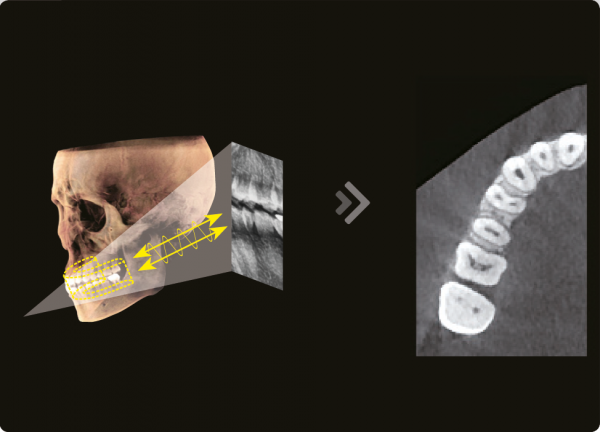

3D и 2D в одной программе

Используя 2D и 3D изображения одновременно мы получаем множество преимуществ. Нет необходимости в двух различных программах , что демонстрирует пациенту более профессиональный подход к диагностике и планированию лечения.